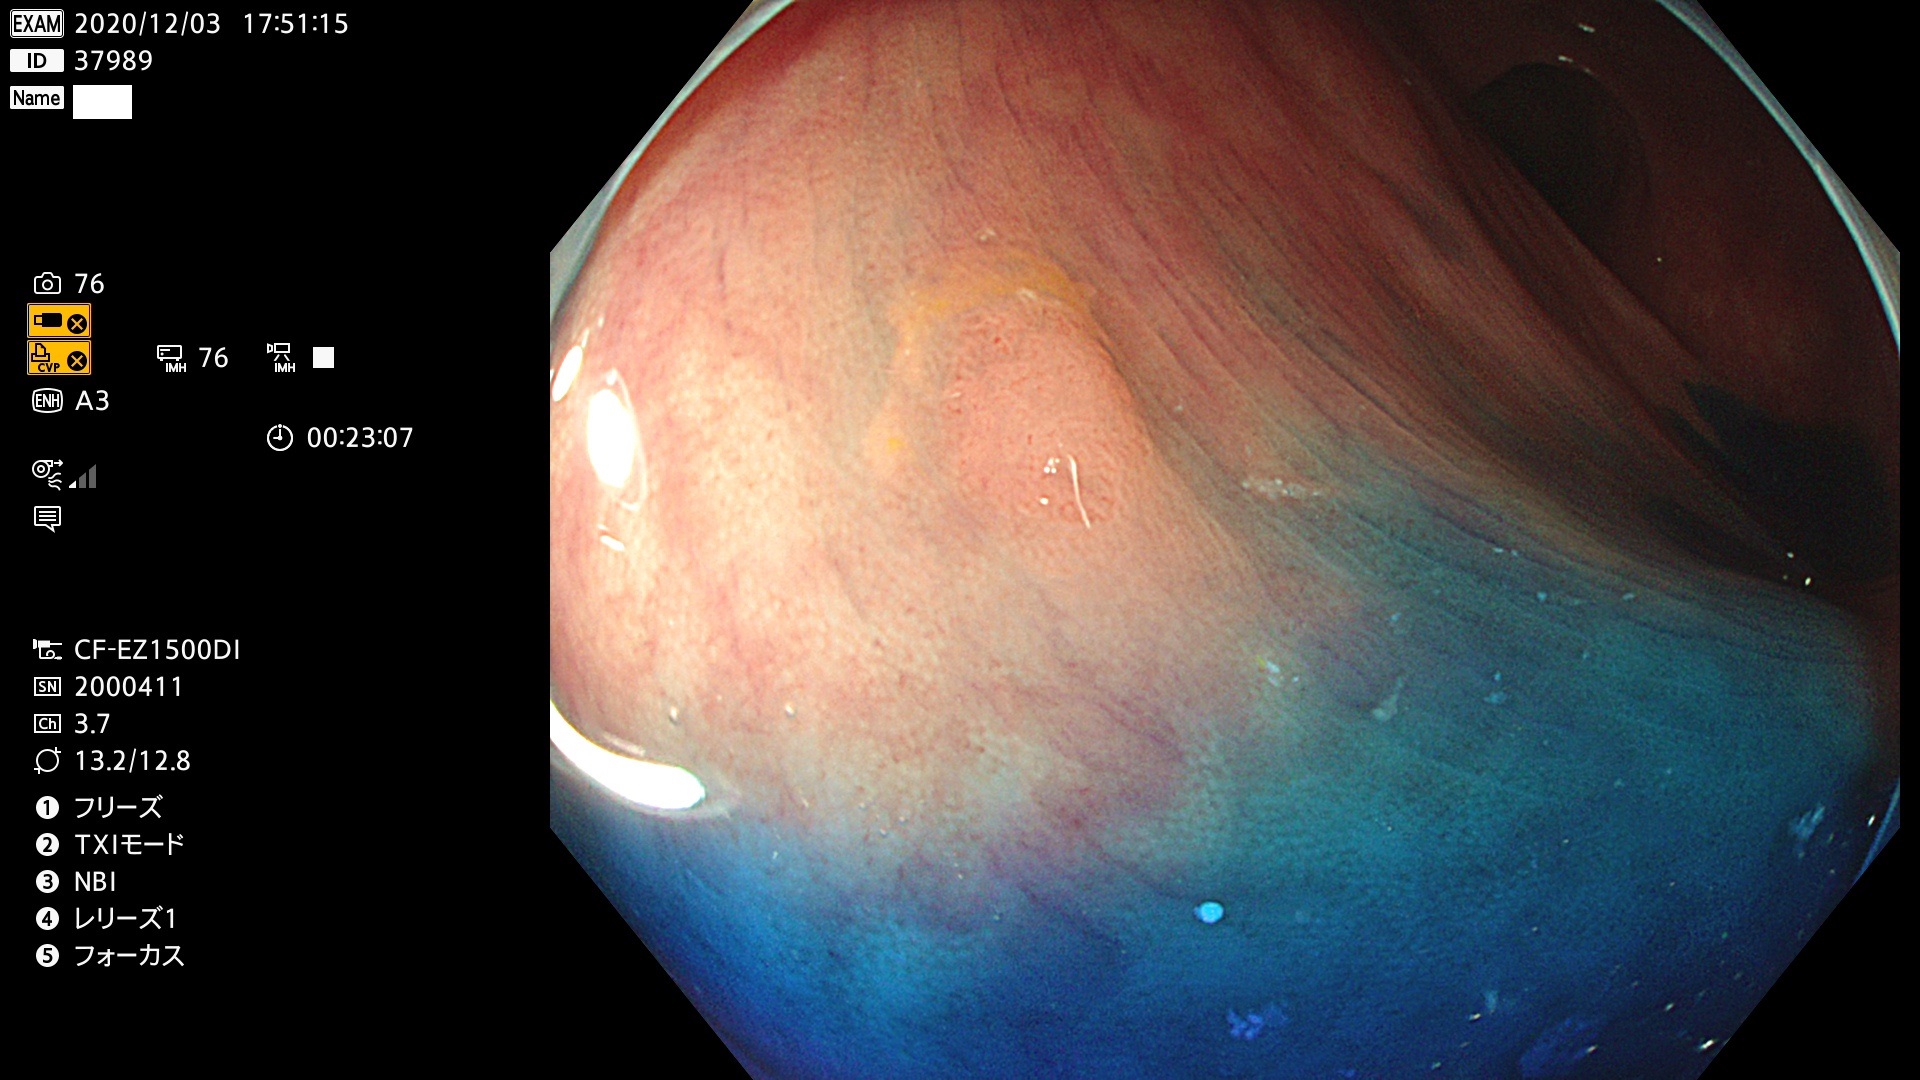

発見困難で危険性の高い平坦型病変(上記100名より抽出)

37900 37902 37903 37904 37905 37906 37907 37909 37910 37911 37912 37913 37914 37915 37916 37917 37919 37921 37922 37923 37926 37928 37929 37930 37931 37933 37934 37935 37936 37937 37938(SSAPのみ) 37939 37940 37941 37942 37943 37946 37947 37948 37949 37951 37952 37953(SSAPのみ) 37955 37956 37957(SSAPのみ) 37958(SSAPのみ) 37960 37962 37963 37964 37966 37967 37968 37971 37972 37973 37975 37976 37977 37979 37982 37983 37984 37985 37986 37987 37988 37989 37990 37991 37992 37993 37994 37995 37996 37998 37999